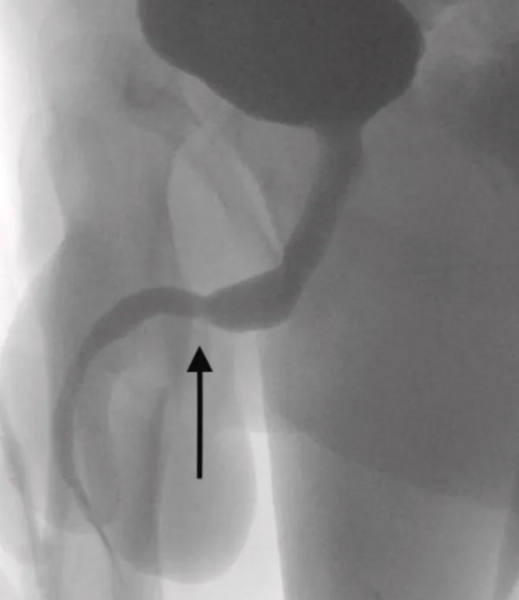

USB kablosu şikayeti ile hastaneye başvuran 15 yaşındaki çocuk Londra Üniversitesi hastanesine kaldırıldı. İsmi açıklanmayan gencin durumu doktor raporların göre "USB kablosunun iki distal portunun dış üretral kanaldan dışarı çıktığı ve düğümlü telin orta kısmının üretra içinde kaldığı tespit edildi. Hasta, ruh sağlığı bozukluğu öyküsü olmayan, aksi halde zinde ve sağlıklı bir ergendi." denilerek açıklandı.

İlk önce metal bir çubukla çıkartılmaya çalışılan kablo daha sonra düğümlendiği için çocuk acil olarak ameliyata alındı. 15 yaşındaki çocuğun Ultrason rehberliğinde suprapubik bir kateter yerleştirildi ve yaklaşık 700 ml hematürik idrarı boşaltıldı. Rapora göre, cerrahlar kablonun bir ucunu anüsüne yakın bir kesiden ve geri kalanını penisinden çıkardı.